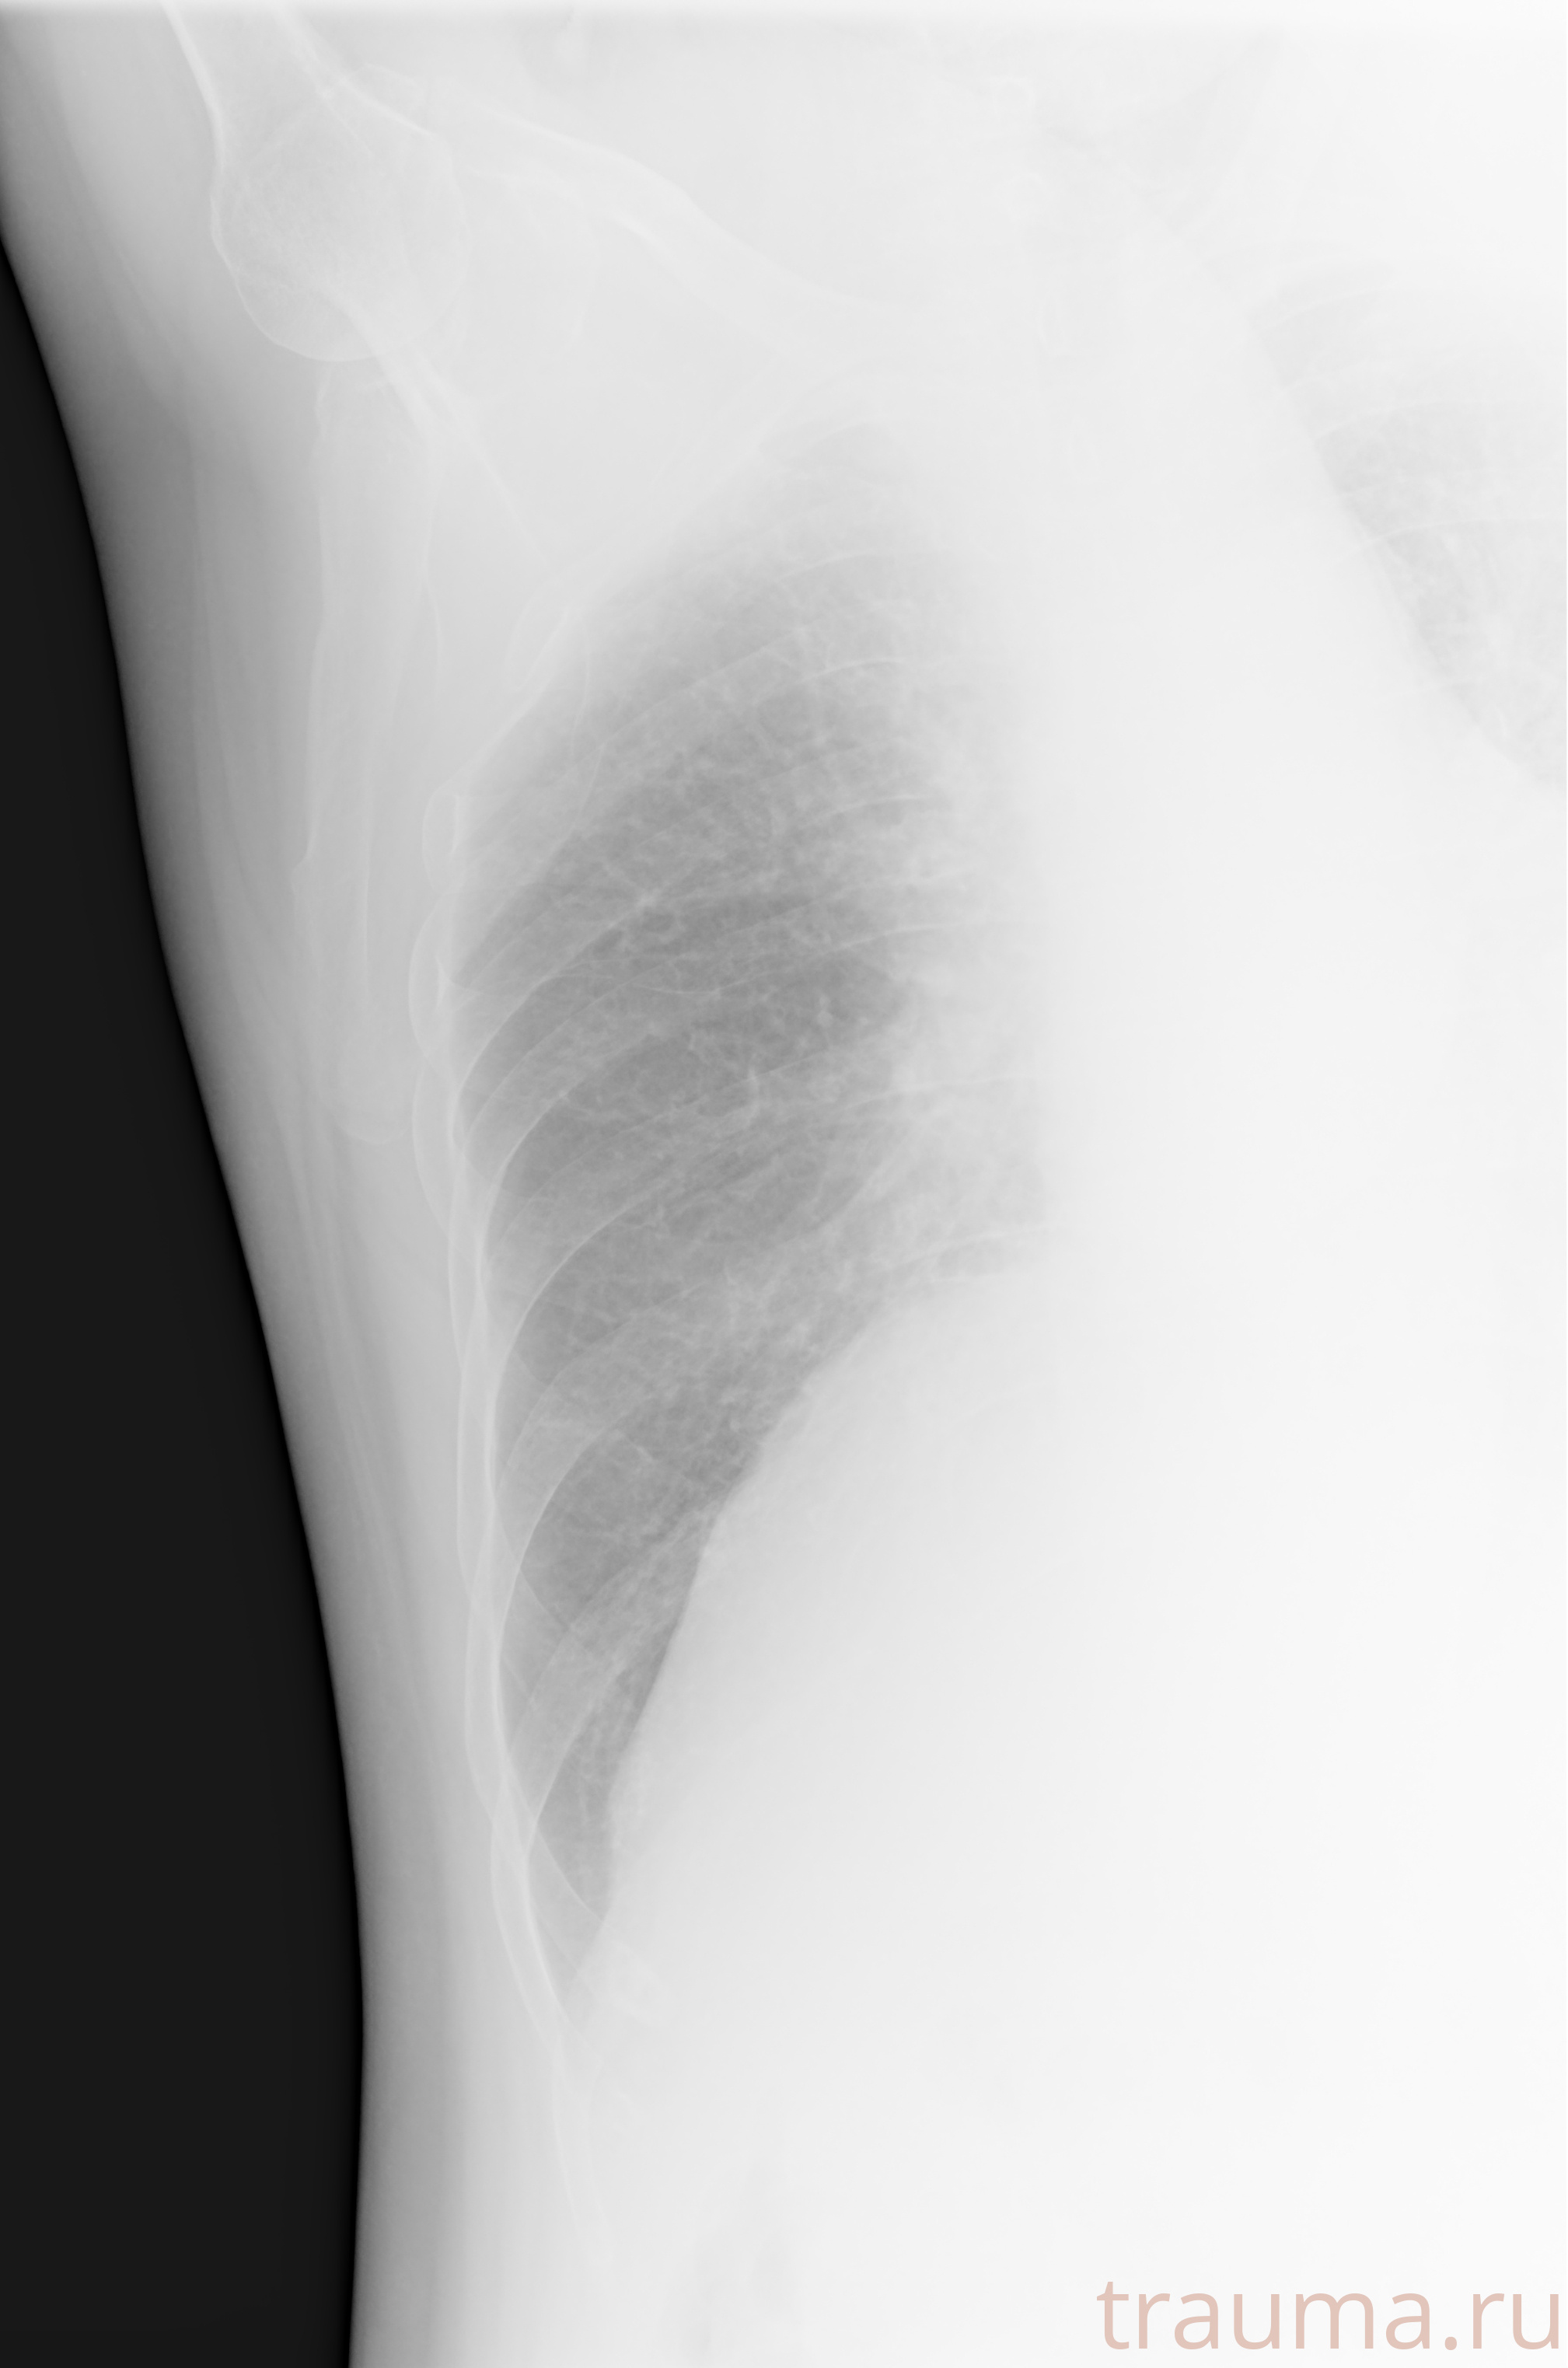

Рентгенограммы

Рентген на дому: по вашему адресу приезжает врач-рентгенолог, травматолог-ортопед с мобильным рентгеновским аппаратом, проводит диагностику травмы или заболевания, делает необходимые рентгенограммы, дает рекомендации по дальнейшему лечению. Получить качественные снимки в домашних условиях возможно благодаря уникальной методике, разработанной МосРентген Центром для института  Склифосовского